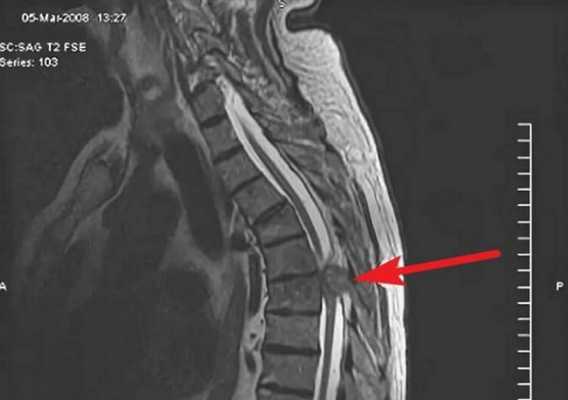

Экстрамедуллярная опухоль спинного мозга на МРТ (обозначена стрелкой) грудного отдела